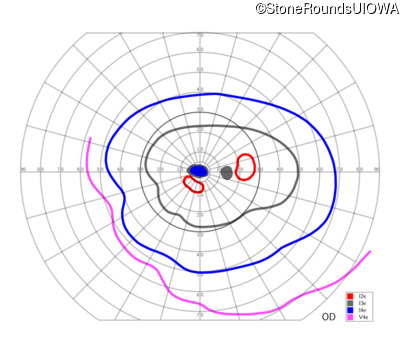

This 52 year old man had normal vision until his mid 30's when he began to have trouble distinguishing colors. the issuing 10 years he had a gradual loss of visual acuity accompanied by increasing photophobia.

| Age at visit: 55 years |

| Age at visit: 58 years |

| Age at visit: 61 years |

| Age at visit: 64 years |